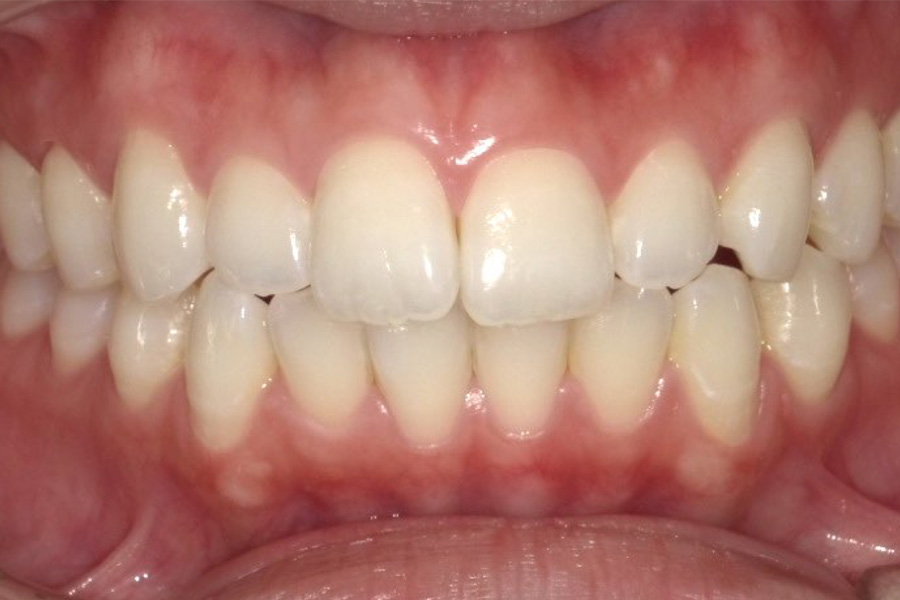

虫歯があるから削ったり悪くなったから抜くのではなく、まずは虫歯と歯周病が起きないようにより良い環境づくりをすること、そうすることによって歯を長く維持することが可能となります。

そのためには、健康状態に関する情報と生活習慣などの状況を把握したうえで、お口の中のリスク評価をおこないます。

その結果をもとに、お一人お一人にあった治療計画をご提案させていただきます。

ご自分の歯で食べ、話し、笑える幸せを生涯にわたり維持するためのお手伝いを全力でさせていただきます。